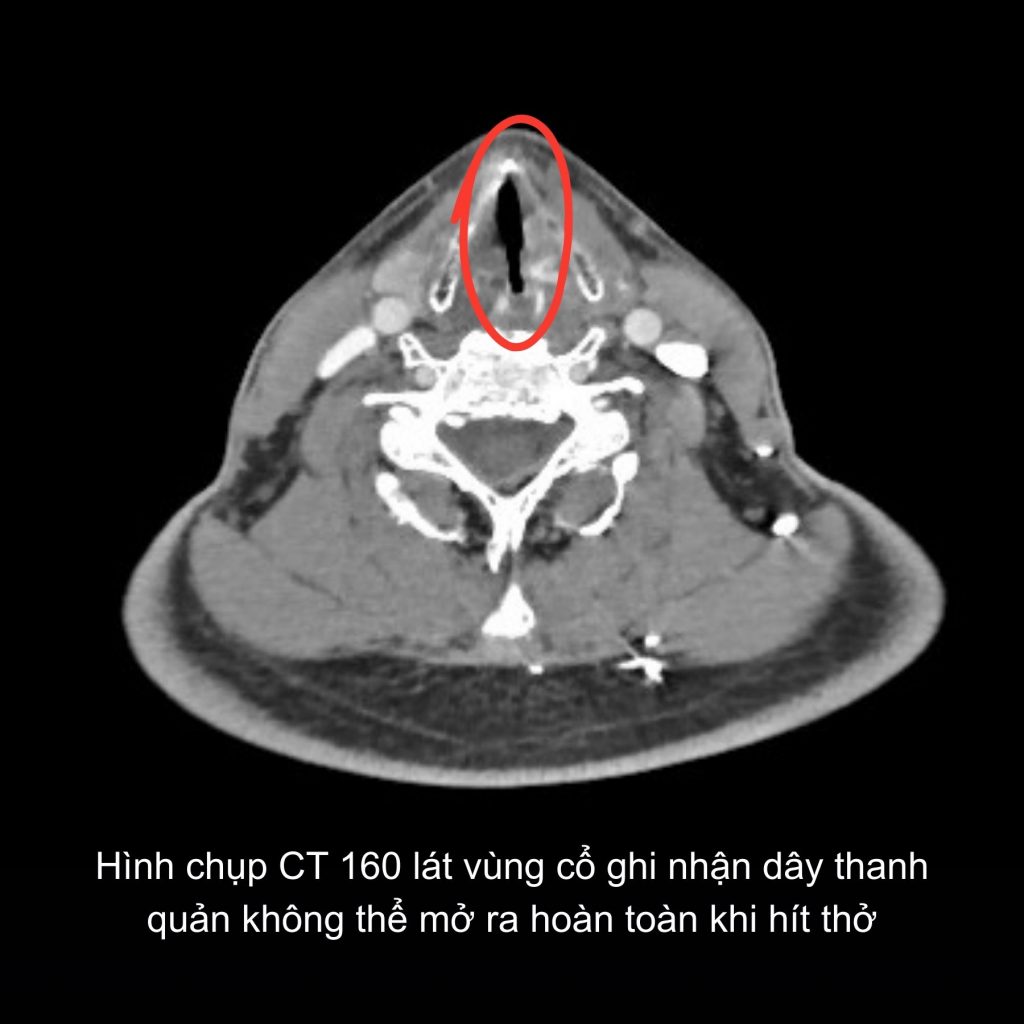

Tại đây, các bác sĩ chuyên khoa Tai Mũi Họng tiến hành soi họng, chụp MRI sọ não và CT cổ ngực. Kết quả ghi nhận liệt khép dây thanh hai bên, khiến dây thanh không thể mở ra để thở. Trước nguy cơ bệnh tiến triển nặng, có thể dẫn đến khó thở cấp và suy hô hấp, các bác sĩ quyết định phẫu thuật cắt 1/2 dây thanh bên phải nhằm mở rộng đường thở, đảm bảo hô hấp cho người bệnh.

Hình ảnh CT của bệnh nhân